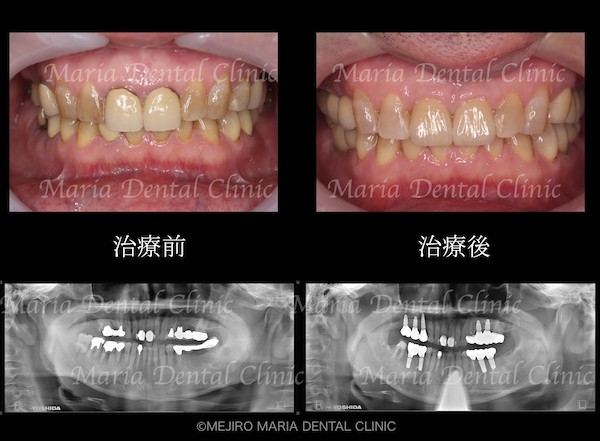

患者様は、長年にわたり臼歯部(奥歯)の噛み合わせの調子が悪いことと、食事の際に痛みを感じることを主訴に来院されました。前歯部から口腔内を確認すると大きなトラブルは確認できませんが、レントゲン撮影と口腔内診査を行うと、多数の臼歯部の歯牙(歯)が歯根破折により抜歯を余儀なくされる状況でした。

まずは、歯周組織検査を含めた口腔内診査、レントゲン写真の撮影により、保存できる歯牙と、抜歯をせざるを得ない歯牙などを選定しました。

今回の症例では、歯根破折していた5本の歯牙(下の写真・赤矢印)に対して、抜歯を提案した。また、診断用WaxUp(ワックスアップ)を行ったところ左下のブリッジ(青丸)と右下(青矢印)の噛み合わせ平面が乱れており、咬合に負担をかけていることが予想されました。そのため、最終的にそれらの不調和を改善し、適切な噛み合わせにすることをゴールとして治療を開始しました。

治療後の様子

各分野の専門医(精密根管治療専門医・インプラント専門医・口腔外科専門医)が最善を尽くすことで、より高度な治療をスピーディーに終えることができました。

最終段階に入る前に、仮歯の状態で咬合の安定が確認できたことから、最終補綴処置を行いました。最終補綴処置後の経過は良好で、今後はメンテナンスをしながらインプラントを含めた根尖周囲組織、補綴物(被せ物)の長期的な経過を確認していきます。